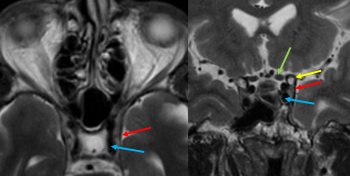

Most patients initially undergo noninvasive imaging with computed tomography (CT), magnetic resonance imaging (MRI), CT angiography (CTA), or magnetic resonance angiography (MRA). The most common neuroimaging signs of anterior draining CCFs include proptosis, enlargement of the SOV, CS, and extraocular muscle enlargement.[30] Enlargement of the IOV and cerebral venous congestion can also seen. If there is a high degree of clinical suspicion or suggestion of a CCF on noninvasive imaging, diagnostic cerebral angiography (digital subtraction angiography, DSA) can confirm the diagnosis and guide treatment.

MRI: Compared to CT, MRI can better demonstrate fat stranding reflecting orbital edema and abnormal flow voids.[33]